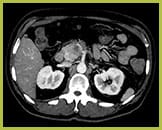

View an anatomical area using different spectral results.

Created by removing the iodine component from the image. Hounsfield Unit (HU) measurements from virtual non-contrast spectral results are comparable to true non-contrast scans for the majority of the organs, allowing VNC results to replace a true non-contrast scan.